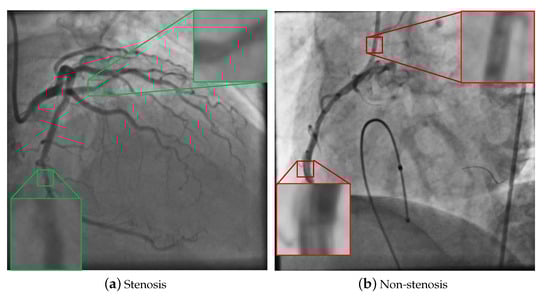

4.1. Databases of Coronary Stenosis